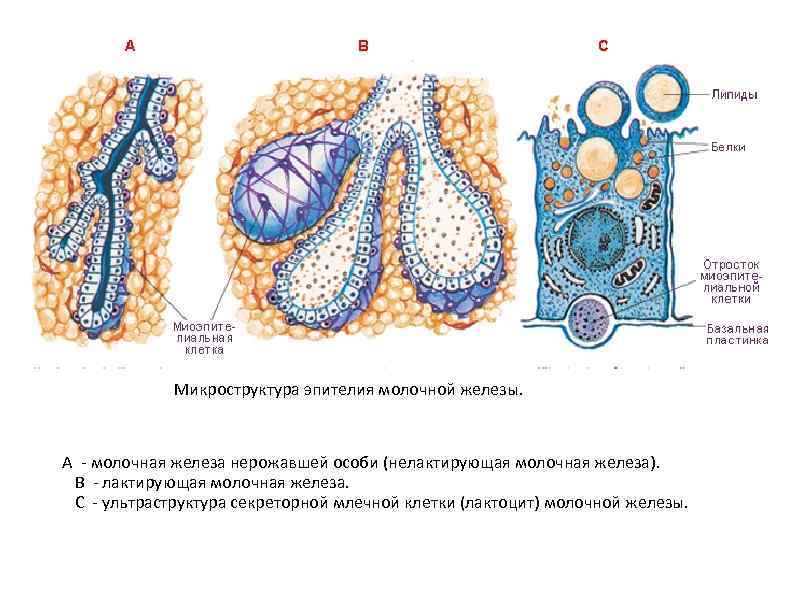

Исследование: микропрепарат молочной железы в медицине

Раздел: Снимки-откровения